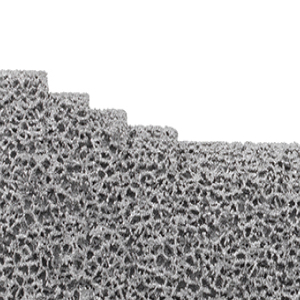

Selon la qualité osseuse, le poids corporel et le niveau d’activité physique du patient, ces composants sont fixés à l’os avec ou sans l’application d’un ciment. Une surface de glissement en polyéthylène est insérée entre les composants tibial et fémoral.

Afin d’augmenter la durabilité des implants, des alliages métalliques spéciaux sont utilisés, certains étant dotés d’un revêtement céramique. Ce revêtement permet également de traiter les patients souffrant de sensibilités à certains métaux.

ChezImplantcast France, nous intégrons des évolutions technologiques dans la conception de nos implants orthopédiques, destinés à une utilisation par les chirurgiens conformément aux indications prévues. Titane en impression 3D, revêtement TiN et traitement de surface Argent pour les prothèses massives.